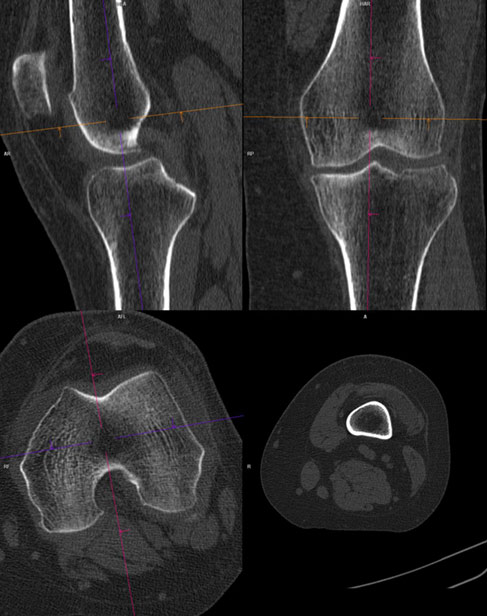

De obicei, pentru articulatii/ oase, se folosesc imagini cu doua tipuri de parametri diferiti: pentru parti moi si pentru os.

Imaginile cu parametri de os (“kernel” dedicat osului) sunt cu conturi mult mai netede, mai exacte, mai “sharp”, care permite o foarte bună apreciere a celor mai fine traiecte de fractură, însă imaginile 3D obținute pe seama acestora nu sunt la fel utile, fiind cu margini ascuțite și un aspect mai puțin plăcut vizual datorită prea multor detalii prezente.